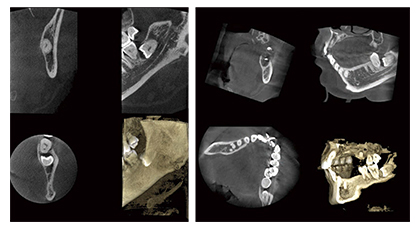

歯科用CTスキャン

歯科用CTスキャンとは

CTとは、Computed Tomography(コンピュータによる断層撮影)の略称です。X線を利用し、体内の断面図を解析、コンピュータ上で再構成し表示します。

従来のX線写真は2次元的な平面での診断しかできませんが、歯科用CTスキャンでは3次元の立体画像でのレベルに変わるのでより多くの情報が得られます。 歯科用CTスキャンはコンピュータを駆使したデータ処理と画像の再構成で、断層写真を得ることができる装置です。

主に、インプラント治療、親知らずの抜歯、歯周病治療、根管歯内療法、矯正歯科などの治療に用いられます。 3次元の高画質画像を用いることで、断層方式パノラマX線写真やデンタルX線撮影法では判別できない、痛みや症状の原因の究明に役立ちます。

歯科用CTの特長

- 医療用CT撮影の10分の1程度まで被爆量を軽減することができます。

- 今まで他の医療機関に出向かないとCT撮影が行えなかった症例でも院内で撮影が行えるため、正確かつ迅速な診療が可能となっています。

- 歯科用CTはインプラントだけでなく歯周病治療や根管治療、口腔外科治療などにも幅広く活用することができます。

- 今まで見つけることのできなかった口腔内の疾患等を発見することが可能です。